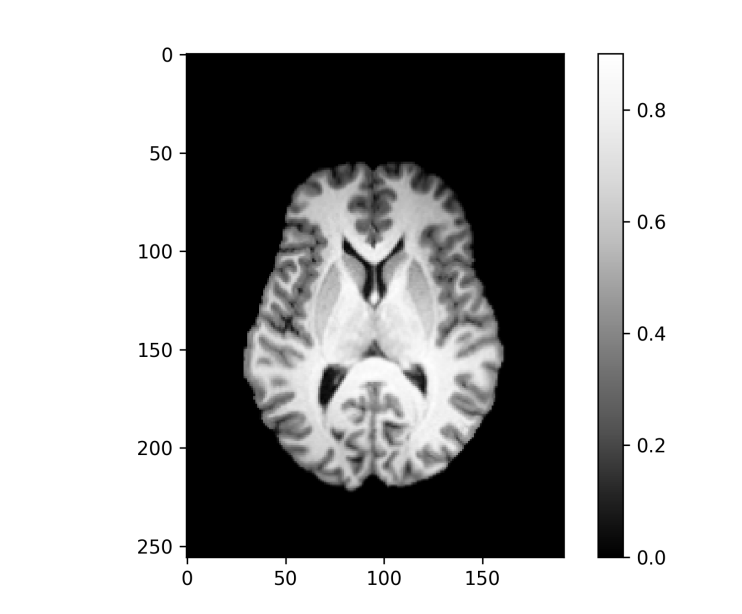

As already mentioned, for real images given on a discrete domain that approximates the underlying continuum , the minimization is performed numerically with a discretized version of the functional . After minimizing the optimal parameters and the template are obtained. The registered images are now aligned with the template. Figure 2 shows an example of a registered sample image for the 3d example dataset from Subsection IV-B together with template images for the - and -norm for affine transformations.

An important application of image registration is the preprocessing of 3d MRI brain images. Here a collection of brain images (possibly from different subjects) are registered with a template, here also called an atlas, which enables more direct comparisons between different brains despite differences in the respective brain geometry before registration. The dataset used here for demonstration purposes is the Neurofeedback Skull-stripped (NFBS) dataset [9], which contains 125 raw MRIs and their skull stripped versions. The intensities of the sample images are normalized such that the median of each image (without the background zeros) is mapped to . Additionally, we are optimizing an intensity scaling factor for each image during the registration such that the scaled template matches the registered image under the similarity metric. This minimizes the vertical variability and brings us a bit closer to the model situation of the shifted edges. The effective height for the resolution measure is chosen as .

For the skull stripped brains a template is generated for affine and rigid transformations and for - and -norm similarity measures, as shown in Figure 10. In each of the four cases the template resolution is computed with Algorithm 1 and horizontal slices of the resulting 3d images of the values are shown in Figure 11 and visualized on top of the template, as described in Subsection III-D, in Figure 12.

Again, the affine registration is more accurate, especially at the boundary of the brain, and the -norm templates appear sharper than the -norm versions but – as revealed by the template resolution measure – are only slightly better in terms of registration accuracy. The rigid registration results are almost identical. In the affine case the -norm leads to better registration at the upper part of the brain (frontal lobe; see Figure 2 for locations), while being similarly inaccurate around the lateral ventricles (twin holes in the lower middle). In all cases the regions in the upper middle of the brain (around the putamen and thalamus) are quite well registered and are also the sharpest regions of the templates across all registration variants. This is in agreement with measurements of the volumes of these brain regions (see e.g. Table 4 in [11] for healthy controls, or Table 2 in [12]) where the coefficients of variation (standard deviation divided by the mean) of the volumes are relatively low for the putamen and thalamus compared with those for the lateral ventricles, the latters’ variability ranging among the highest across all measured regions.